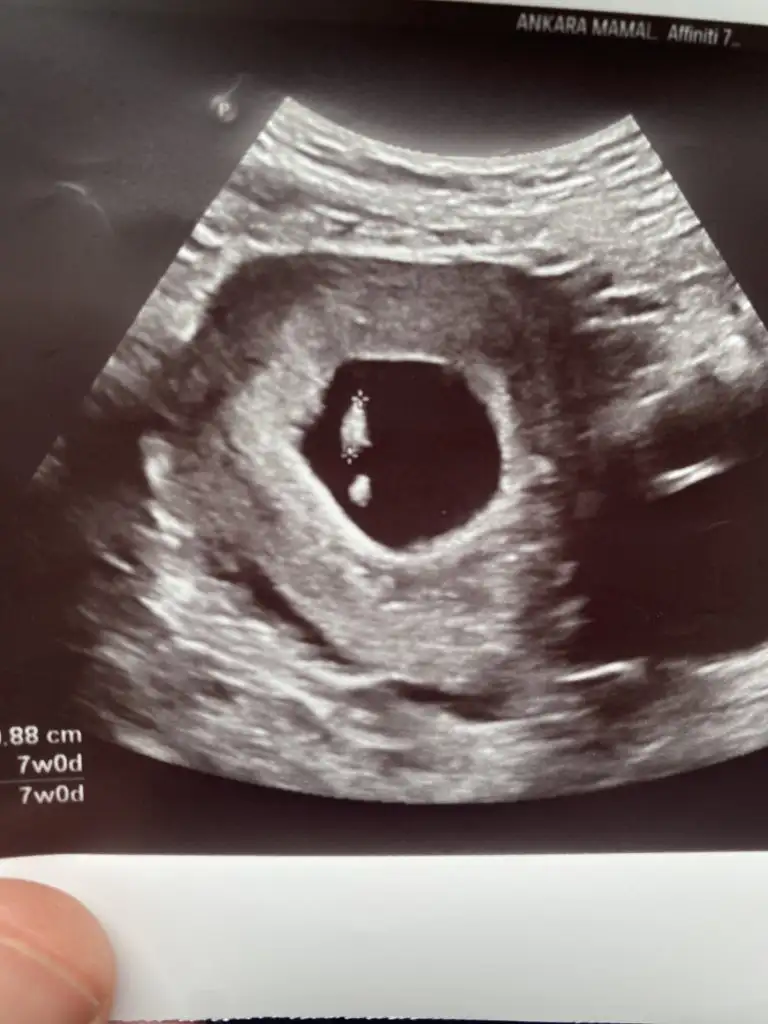

Meraba hanımlar bende bugün gittim doktora 7 haftalık hamileyim karından usg ile görüntümü atıyorum tahminde bulunurmusunuz

Eklentiler

• IMG_2752.webp

IMG_2752.webp

25,9 KB · Görüntüleme: 91